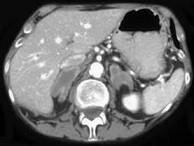

问题 男,65岁,体检时超声发现双侧肾上腺肿块,CT检查如图所示,请结合图像,选择最佳答案 ( )

选项 A、双侧肾上腺增生 B、双侧肾上腺腺瘤 C、双侧肾上腺结核 D、双侧嗜铬细胞瘤 E、双侧肾上腺转移瘤

答案 E